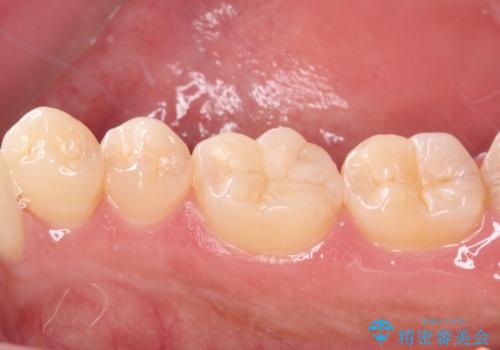

精度の高いセラミックインレーにて修復処置することとしました。

噛んだ時の痛みや、冷たいものがしみる症状はなくなり、見た目も自然でどこが詰め物かわからないと、患者様は大変満足されました。